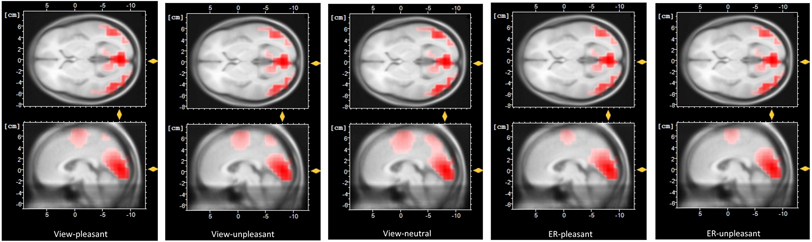

Table 4 shows the mean ERP waveform values per condition and group. Figure 3 shows how the effects of the different conditions are distributed across the scalp, showing a clear posterior pattern for all experimental conditions. The ERP waveforms at the Pz electrode are shown in Fig. 4.

Fig. 3

Averaged topography (400–800 ms) in response to the view-neutral condition and the experimental conditions: view-pleasant, view-unpleasant, ER-pleasant, ER-unpleasant